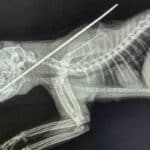

The National Parks Board discovered the pet’s carcass on February 2, 2021, and a post-mortem examination indicated the cat had died from self-digestion – a condition where dying cells digest themselves from starving, according to Channel News Asia.